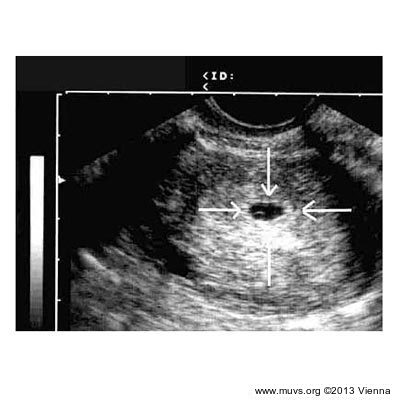

In some discussions, certain features of early stages in the foetus’ development are often equated with fully developed organ systems. For example, the heartbeat: twenty-eight days after the embryo attaches to the uterus wall, muscle cells in a blood vessel that will eventually develop into the heart begin to pulsate. But a great deal has to happen before an actual heart appears: in the beginning, the cells’ pulsation causes nothing more than movement of the blood back and forth. The heart’s musculature is not yet developed, nor has it taken on its final form. The cardiac cavity must first divide from the blastocoel and the two lung buds must separate, after which the foetus’ growth will cause the heart bud to migrate to what will become the thoracic cavity, and atria, cardiac chambers and heart valves begin to take shape. Instead, romanticised descriptions of the baby’s development merely say: “Near the end of the third week, the heart is fully developed and begins to beat.”